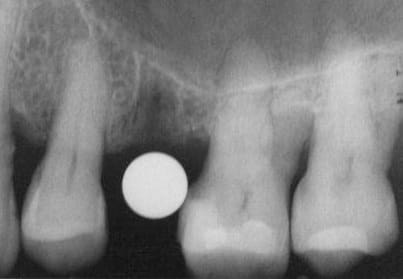

je voulais parler de ce fact pour les implants courts:minimum 4mm os vertical peut suffire (pour eviter un sinus lift externe de tatum) . dans ma pratique depuis quelques années je vois que ca marche , quelques cas cliniques des années passées.

j´ai oublié : 4mm plus 2mm( gagnés par un sinus lift interne)

oui effectivement c est preferable des implants pas agressifs, sur la photo 7 on se rends plus compte que la pointe est plate...